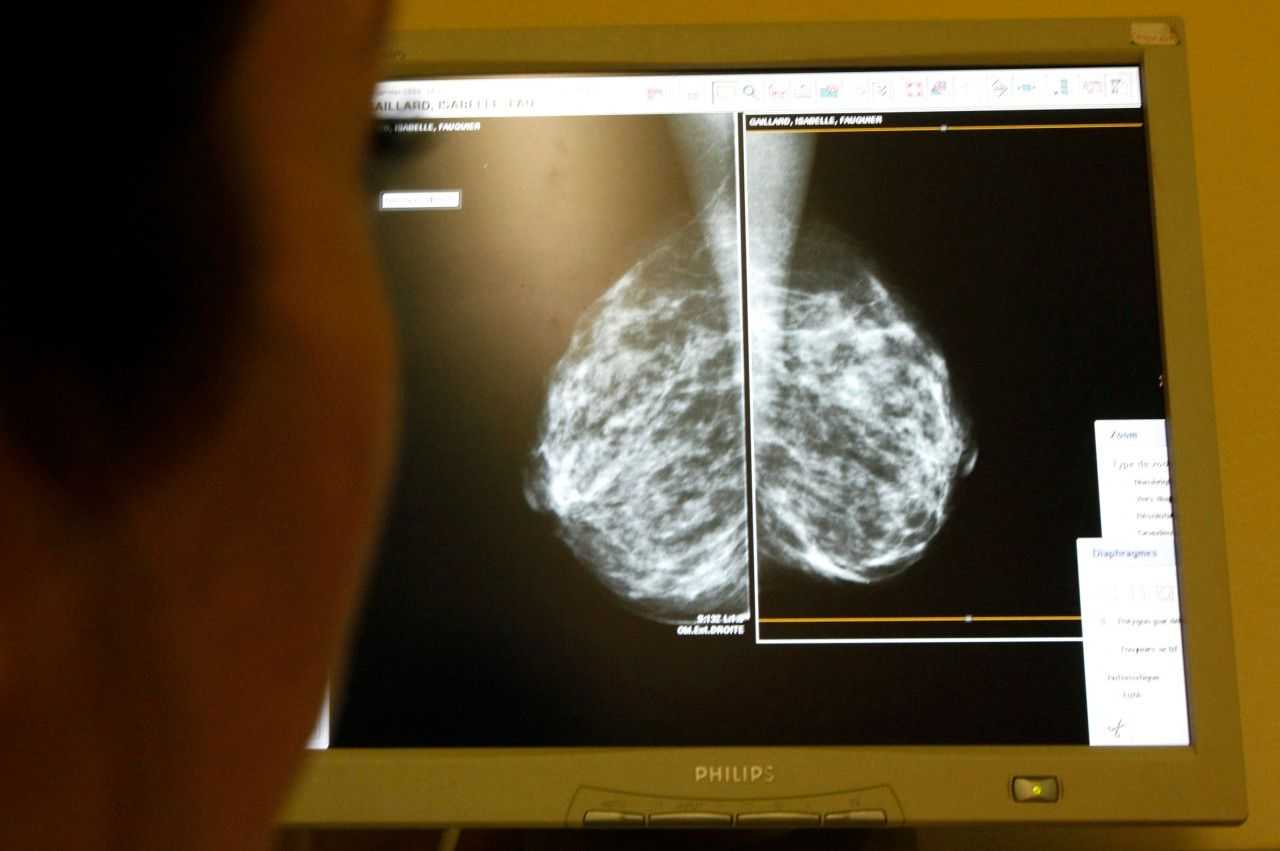

Для постановки точного диагноза необходима консультация у маммолога, который назначает ряд обследований. Для начала проводят ультразвуковое исследование, магниторезонансную томографию и маммографию, что позволяет дифференцировать инвазивную карциному неспецифического типа, поскольку симптоматика схожа.

УЗИ считается наиболее информативной мерой, которая не несет опасности для пациентки. Такая методика дает возможность определить заболевание на первоначальных этапах формирования, при этом назначается необходимая терапия. Для более точной картины назначается томография очага поражения.